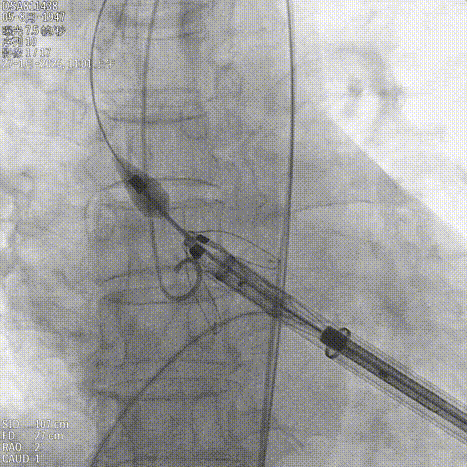

释放瓣膜

锁丝脱钩

撤出输送器

25球囊后扩